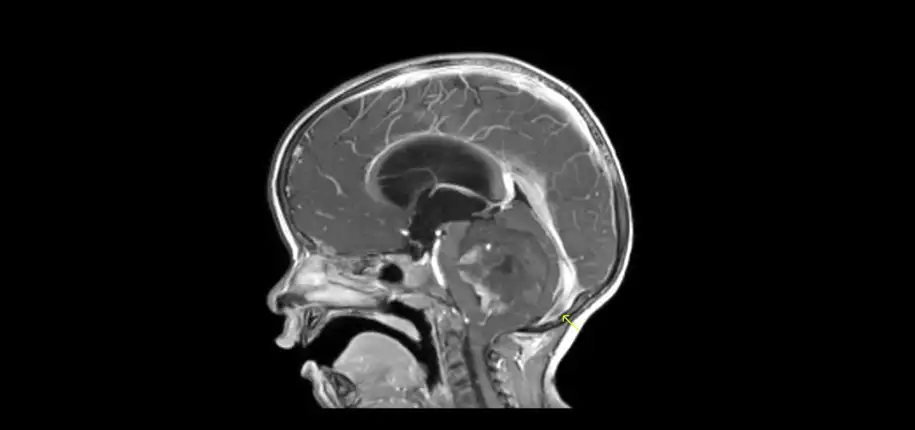

MR contrast is a medicine that is injected into the veins during the MRI scan to increase the ability to see abnormalities. There are some things that will show up after giving contrast that you cannot see without it. Generally speaking, it is helpful if there is a tumor or infection. So for kids with known tumors or infections, or with symptoms that suggest there may be a tumor or infection, it is wise to give contrast during the MRI study. But for other children, giving contrast may only increase costs, time, and risks.